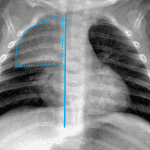

Age: 3 months

Sex: Male

Indication: Fever

- Mild hyperinflation and peribronchial thickening without focal airspace opacification or pleural effusions

- Normal thymus overlying the right lung apex

- Normal thymus

Mild hyperinflation and peribronchial thickening without focal airspace opacification or pleural effusions, which can be seen with a viral infection.

Normal thymus overlying the right lung apex.